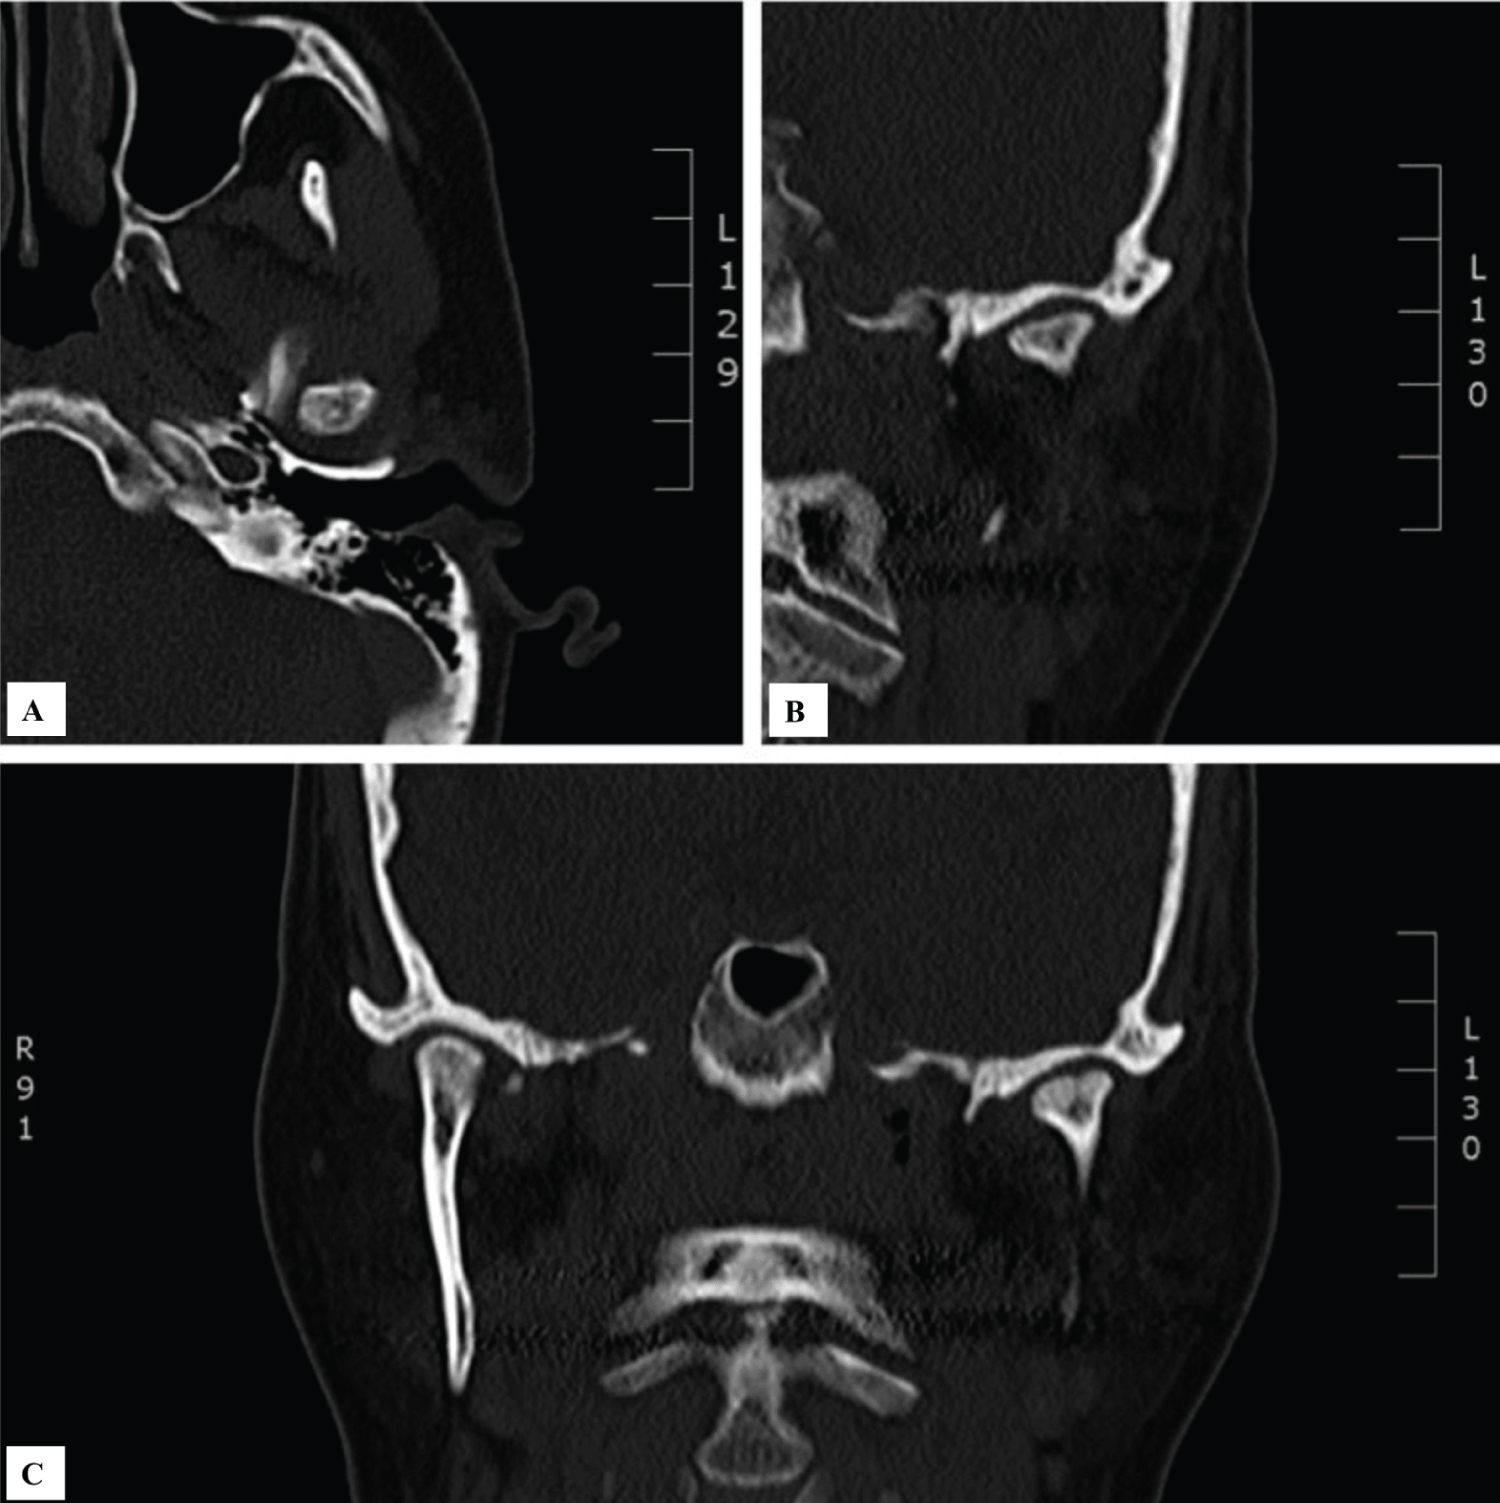

Efficacy was determined by both objective and subjective measurements to include pain at rest and during mastication measured using a visual analog scale (VAS), maximal incisal opening, and radiographic changes to the bony morphology of the TMJ complex (Figure 1). The primary analysis compared the preoperative measures with those at the last follow up visit. Analytical statistics were computed to assess pre- and postoperative differences and radiographic bony changes were evaluated by a radiologist. A paired t test was used to test significance in this study as the small sample size limited the use of other significance tests (n < 30).

Figure 1: Preoperative computed tomography of a 63-year-old female patient with severe degenerative joint disease of the left temporomandibular joint (A) Axial view demonstrating cortical irregularity and bony erosion along the medial aspect of the left condylar head; (B) Coronal view again demonstrating degeneration at the left condylar head; (C) Coronal view again demonstrating degeneration at the left condylar head. View Figure 1